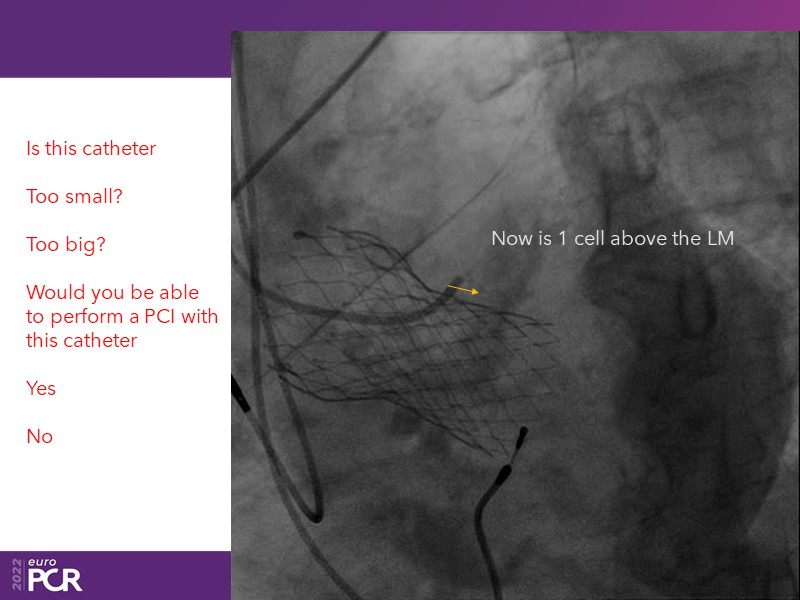

Consult this session to learn how to contribute to streamlined pre- and post-TAVI patient pathways, to discover updates on the optimised TAVI procedure and appreciate the variances in different valve designs and the long-term patient outcomes, as well as to discuss the right time of PCI in TAVI patients (steps on the procedure).

- To discuss the right time of PCI in TAVI patients (steps on the procedure)